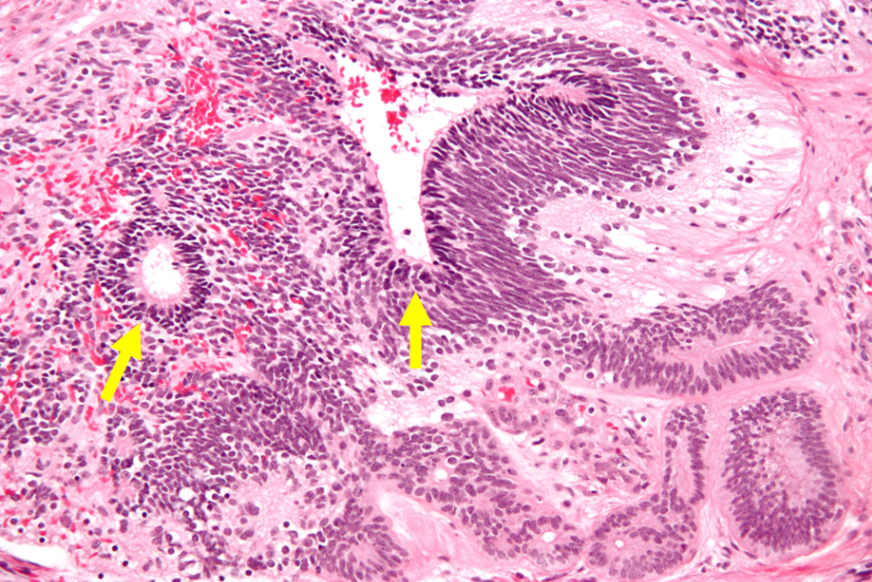

(2) 병리검사: Large cells, large/irregular nuclei, abundant/clear cytoplasm

② 병리검사: 납작해진 불규칙적 endothelial tissue가 다수 확인됨 (Schiller-Duval bodies)